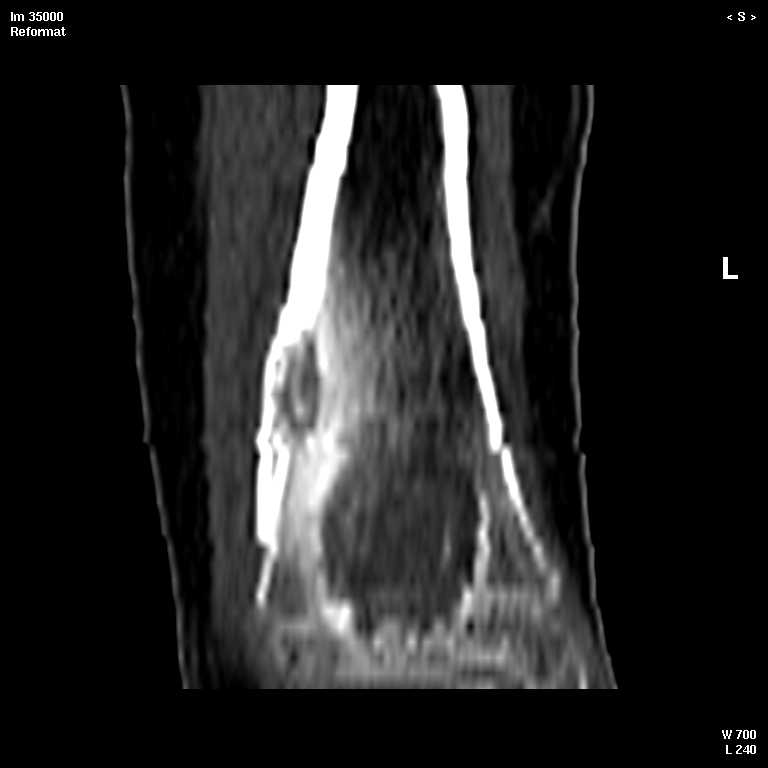

КТ изображения передаю на мой взгляд самые демонстративные. Их любезно записал коллега,

проводивший исследование в другом городе.

Прошу прощения за немного некоректную отправку КТ-снимков но по другому не получается :)

5